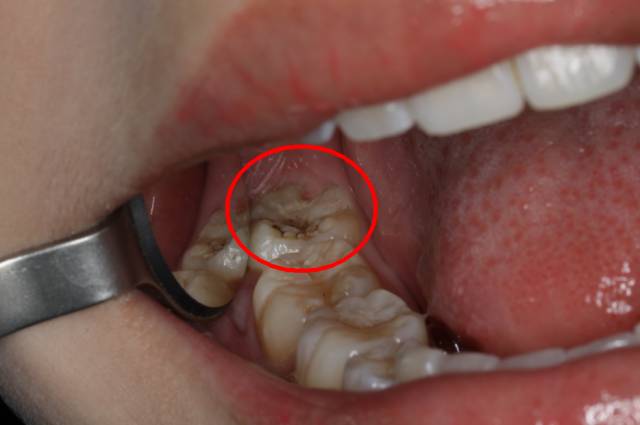

智齒萌出位置唔正,即使冇頂壞鄰牙,都可能同鄰牙形成間隙,產生局部嘅“衛生死角”,食物殘渣同細菌堆積喺嗰啲位,我哋日常刷牙好難清潔到,久而久之就容易引發齒蝕

上图就是一个很典型的例子:看似好像长得还不错的两顆智齿,其實因為位置關係,唔能好好清潔到、都缺乏正常咬合關係,經常會有食物卡住、龍齒嘅發生,等到自己有症狀嘅時候通常都好嚴重。